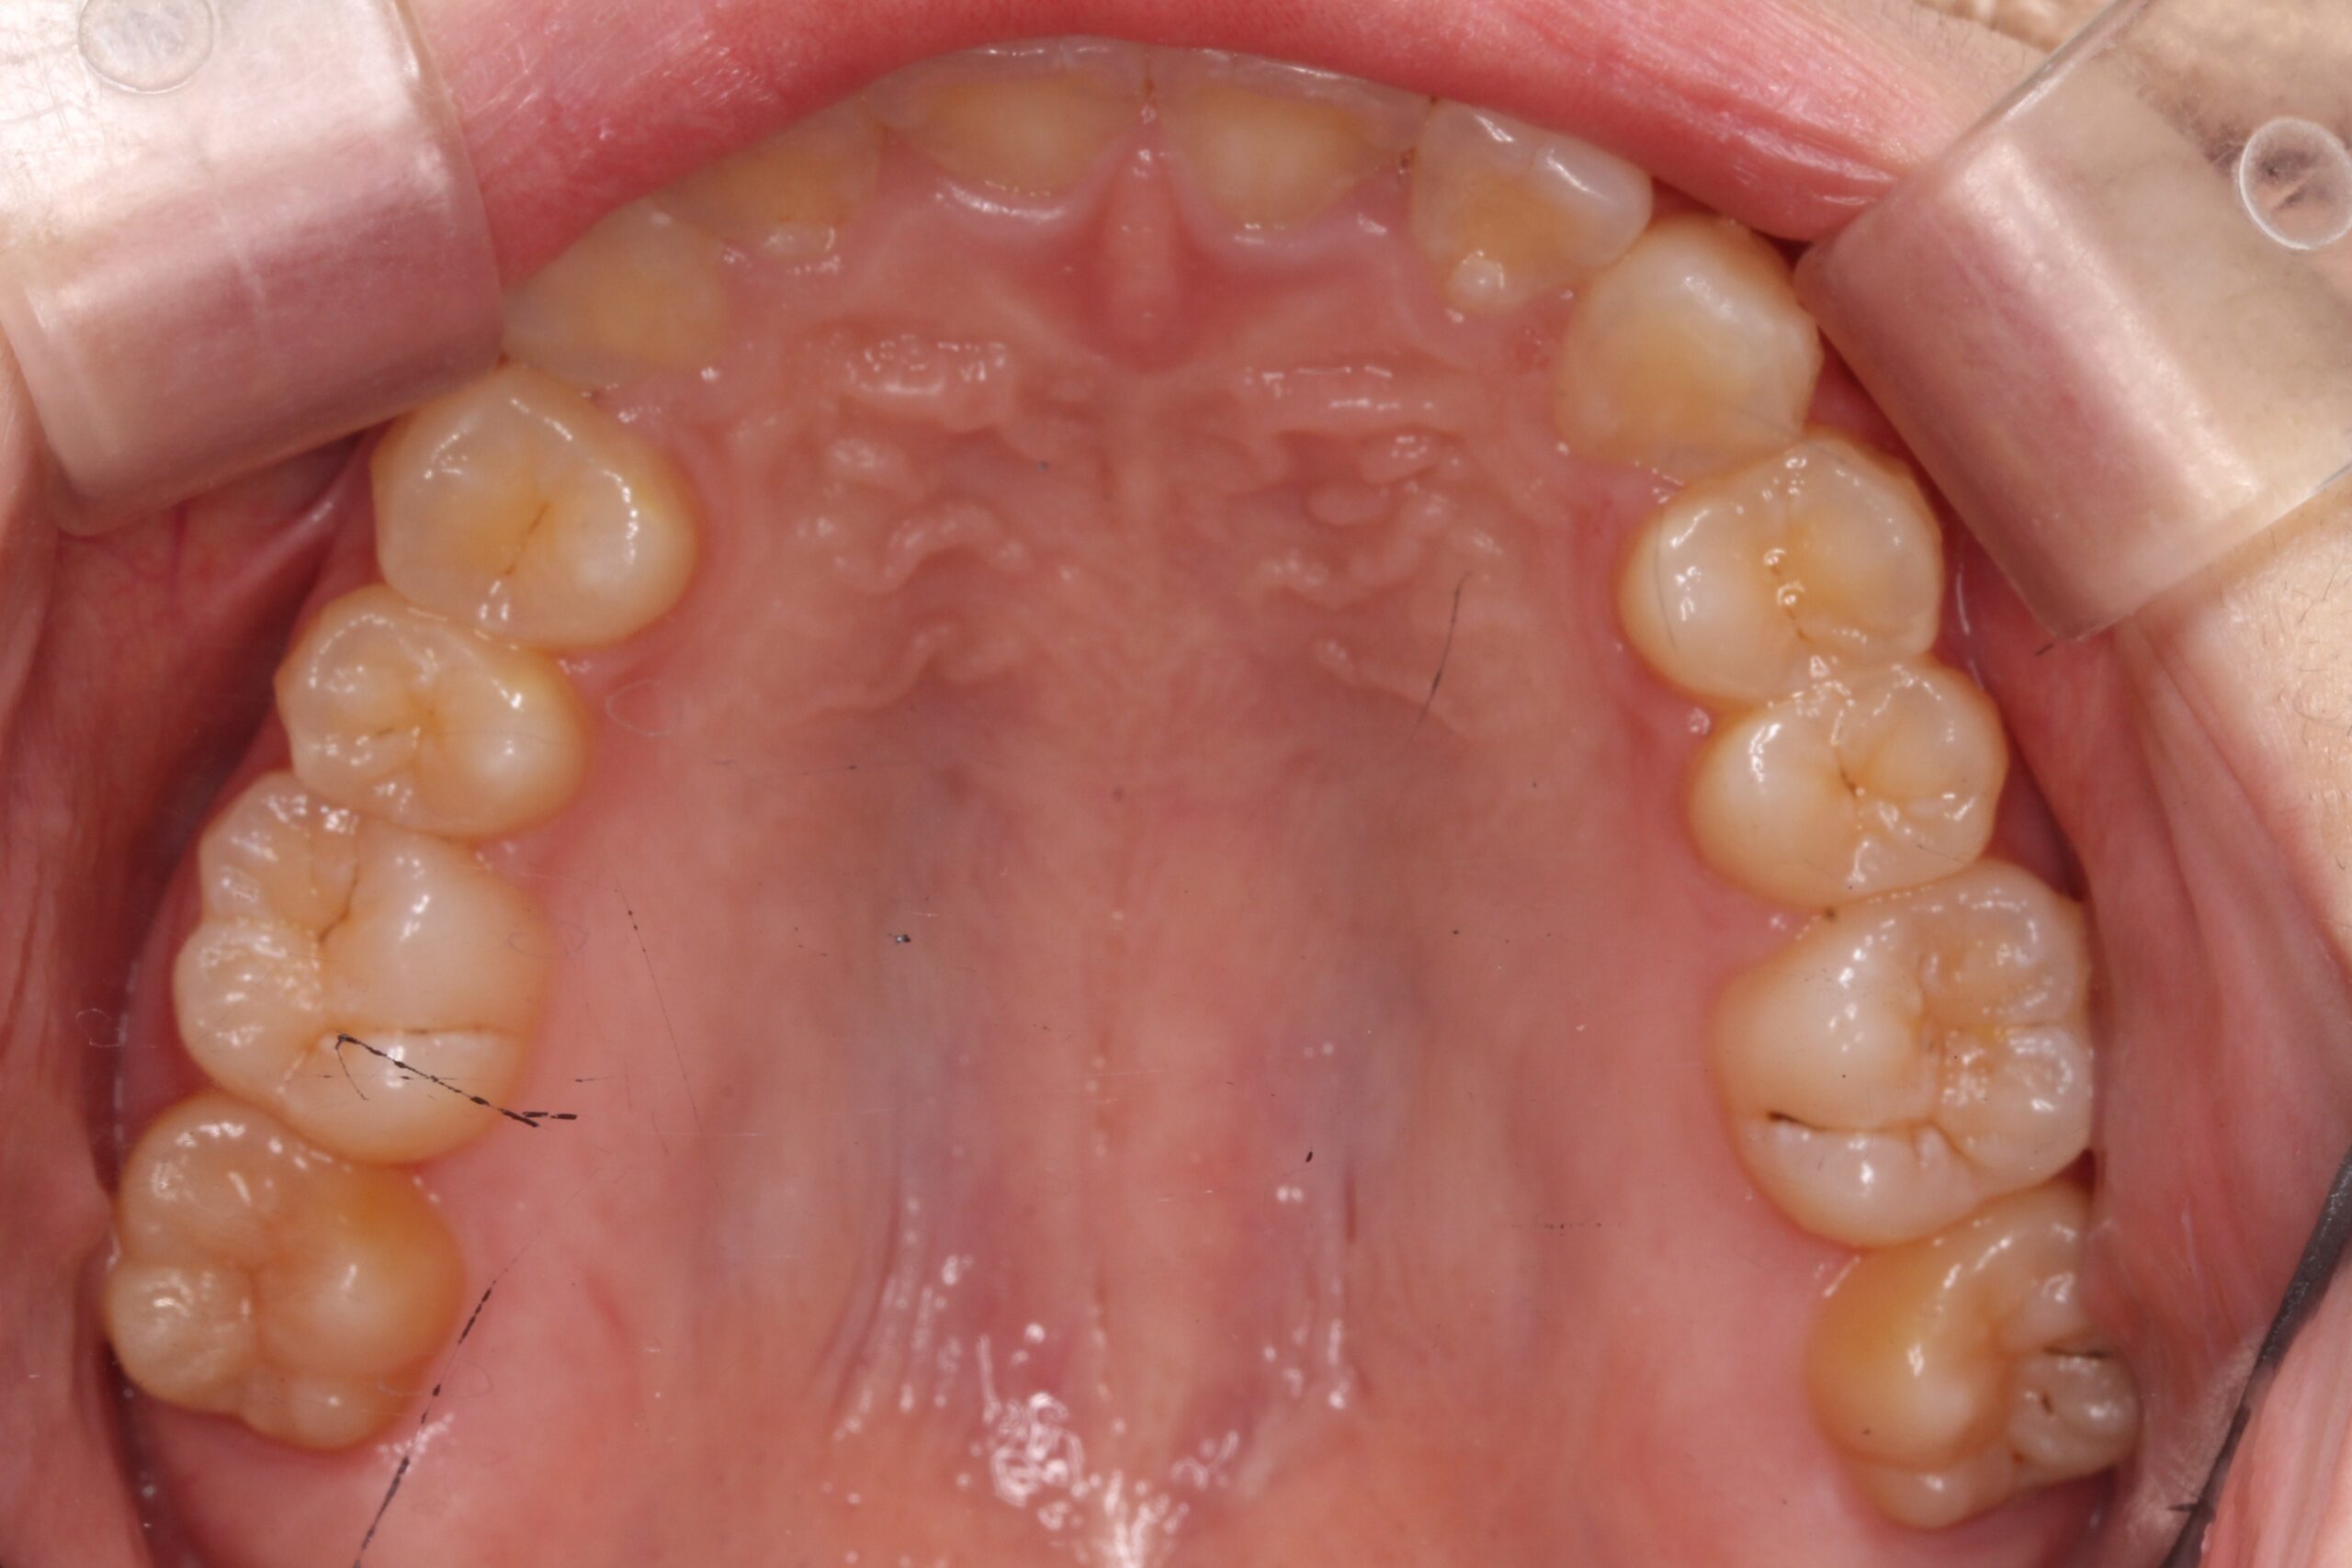

矯正術前:下顎

矯正術後:下顎